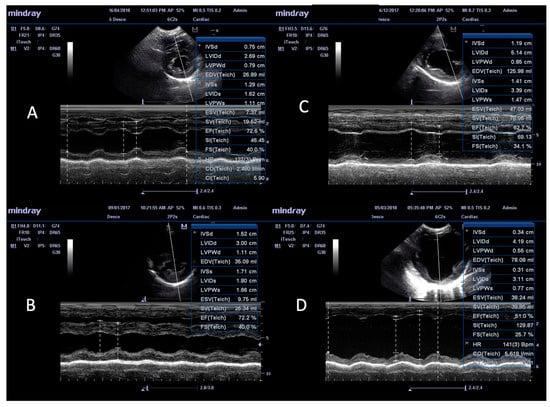

3.3. M-Mode Ultrasonographic Findings

| Parameters | Mode | A (n = 23) | Aw (n = 3) | B (n = 6) | C (n = 86) | Cw (n = 12) | Controls (n = 16) |

|---|---|---|---|---|---|---|---|

| A: Structural features | |||||||

| IVS diastole (IVS-d) * 1 | M mode | 0.5 ± 0.07 a | 0.51 ± 0.05 | 0.4 ± 0.08 | 0.49 ± 0.08 b | 0.4 ± 0.08 a,b | 0.44 ± 0.07 |

| IVS systole (IVS-s) * 1 | M mode | 0.69 ± 0.01 | 0.66 ± 0.05 | 0.67 ± 0.17 | 0.7 ± 0.15 | 0.64 ± 0.18 | 0.64 ± 0.09 |

| LVID diastole (LVID-d) * 2 | M mode | 1.44 ± 0.24 a | 2.02 ± 0.16 a,b | 1.57 ± 0.20 b,c | 1.35 ± 0.25 b,c,d | 2.05 ± 0.15 a,c,d,e | 1.55 ± 0.1 b,d,e |

| LVID systole (LVID-s) * 2 | M mode | 0.83 ± 0.18 a | 1.15 ± 0.10 a,b | 0.91 ± 0.13 c | 0.76 ± 0.2 b | 1.23 ± 0.19 a,c | 0.86 ± 0.1 b |

| LVPW diastole (LVPW-d) * 2 | M mode | 0.51 ± 0.09 a | 0.39 ± 0.16 a | 0.34 ± 0.03 a,b | 0.49 ± 0.1 b,c,d | 0.4 ± 0.09 a,c,d,e | 0.47 ± 0.06 b,d,e |

| LVPW systole (LVPW-s) * 2 | M mode | 0.71 ± 0.09 a | 0.62 ± 0.18 | 0.53 ± 0.11 a,b | 0.73 ± 0.12 b | 0.69 ± 0.19 b | 0.68 ± 0.08 b |

| EPSS 1 (cm) | M mode | 0.39 ± 0.21a | 0.93 ± 0.13 b | 0.5 ± 0.2 | 0.31 ± 0.21 b,c | 0.96 ± 0.09 a,c,d | 0.27 ± 0.11 b,d |

| LA/Ao 1 ratio | B mode | 1.39 ± 0.51 a | 1.69 ± 0.51 | 1.38 ± 0.17 | 1.25 ± 0.24 b | 1.86 ± 0.43 a,b,c | 1.19 ± 0.14 c |

| SI 1 ratio | B and M mode | 1.99 ± 0.21 a | 1.54 ± 0.1 b | 1.87 ± 0.19 | 1.97 ± 0.24 b,c | 1.53 ± 0.08 a,c | 1.75 ± 0.07 a,c |

| B: Functional features | |||||||

| Fractional shortening (FS), % ** 1 | M mode | 40.35 ± 6.66 | 40.33 ± 5.69 | 38.83 ± 5.03 | 41.39 ± 11.2 | 37 ± 10.72 | 41.75 ± 5.36 |

| Ejection fraction (EF), % ** 1 | M mode | 72.61 ± 7.69 | 71.2 ± 7.30 | 68.33 ± 7.51 | 72.75 ± 12.58 | 64.17 ± 14.1 | 74.09 ± 6.68 |

| Stroke volume (SV), mL ** 1 | M mode | 20.85 ± 14.37 a | 33.52 ± 14.77 | 27.49 ± 26.35 | 22.17 ± 15.5 b | 51.18 ± 28.4 a,b | 24.01 ± 10.97 |

| Heart rate 1 | M mode | 102.43 ± 17.98 | 121 ± 8.54 | 95.33 ± 8.71 | 102.5 ± 31.57 | 121.25 ± 41.29 | 108.75 ± 23.95 |

| Cardiac output (CO), L/min ** 1 | M mode | 2.1 ± 1.31 a | 4 ± 1.53 | 2.63 ± 2.52 | 2.22 ± 1.55 b | 6.6 ± 5.13 a,b | 2.46 ± 0.81 |

| E/A ratio 1 | PW Doppler | 1.53 ± 0.34 a | 1.24 ± 0.24 | 1.35 ± 0.26 | 1.37 ± 0.34 | 1.41 ± 0.61 | 1.1 ± 0.29 a |